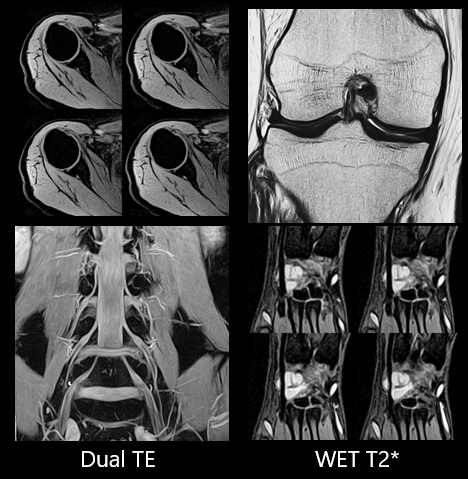

Скелетно-м’язова система